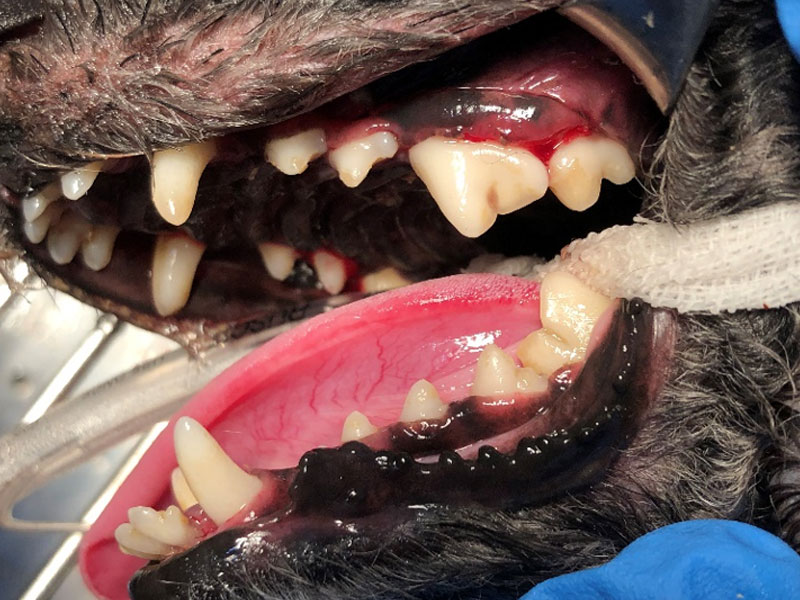

洗牙前,牙結石多

沖刷牙結石,以及確認牙齒的狀況(搖晃、齒根外露)

洗牙後,將牙結石處理乾淨,可見表面潔白光亮

拔牙、搖晃的牙齒、齒根外露